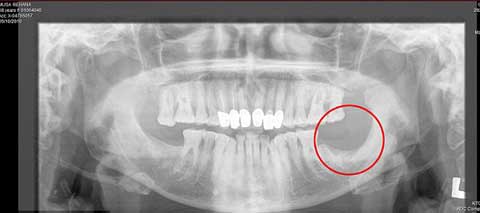

Bà Rehana Musa, 72 tuổi, người Anh đã kiện Bác sĩ nha khoa của mình là Piotr Pietrusczak, vì bác sĩ này đã không kiểm tra tiền sử bệnh của bà trước khi nhổ một chiếc răng khôn vào năm 2008.

Bác sĩ đã phải cắt bỏ cả 1 phần xương hàm của bà Musa để giúp Bà hết đau nhưng cũng không hiệu quả

Bà Musa cho biết lý do bà phải đến gặp bác sĩ để yêu cầu nhổ chiếc răng khôn là do chiếc răng đó cọ xát với má khiến chảy máu rất nhiều.

Trước khi đi nhổ răng, bà Musa đã cẩn thận tới Bệnh viện Derbyshire Royal để kiểm tra, các bác sĩ ở đây sau khi làm lành vết thương ở má của bà cũng khuyên bà nên nhổ chiếc răng khôn để tránh làm tổn thương cho má. Các bác sĩ đã viết sơ lược về tiền sử bệnh của bà để bác sĩ nha khoa sẽ lưu ý trước khi nhổ răng.

Vài ngày sau khi nhổ răng, bà bắt đầu bị những cơn đau nhức liên tục hành hạ. Vết thương trong chỗ nhổ không thể tự lành được mc dù bà đã phải dùng rất nhiều phương pháp giúp làm lành, thậm chí cả một phần xương hàm của bà cũng được bỏ đi để giúp bà thoát khỏi sự đau nhức do vết thương nhổ răng để lại.